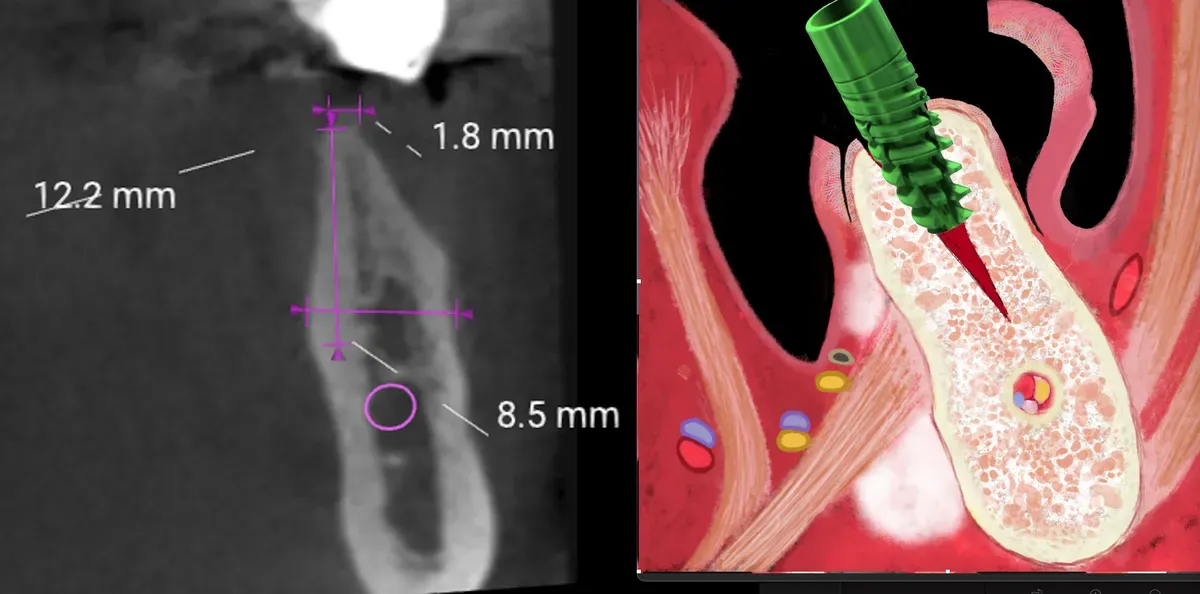

La sopravvivenza implantare raggiunge il 98.1% con intervallo di confidenza al 95% tra 96.9% e 98.9%. Il guadagno osseo medio ottenuto con le tecniche di espansione crestale si attesta a 3.3mm, con un range che va da 1.6mm a 5.3mm a seconda dei casi. Le complicanze risultano gestibili quando si applica la tecnica appropriata.

La verità: Le linee guida BDIZ EDI dicono che l’atrofia H3 controindica l’espansione.

I limiti esistono ma sono diminuiti:

L’osso A1 mandibolare è difficile ma fattibile con spugnosa centrale. La rigenerazione verticale funziona bene per casi lievi come la classificazione V1 secondo BDIZ EDI. Le creste a clessidra no, la cresta deve allargarsi progressivamente.